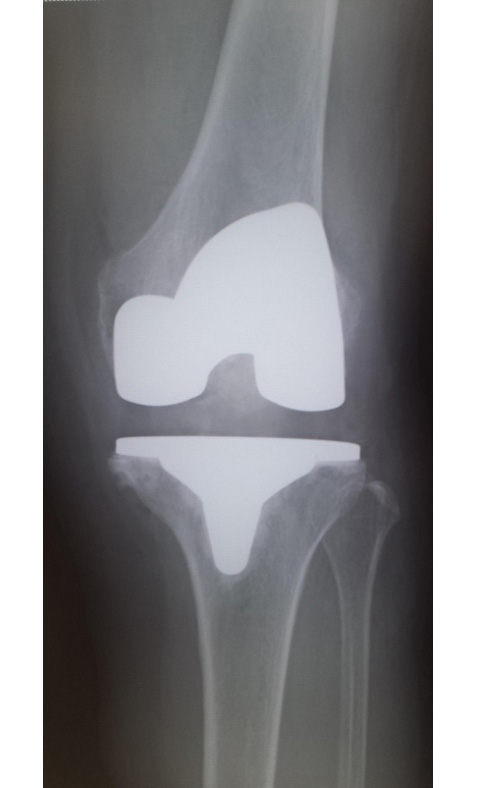

当院でおこなった人工膝関節全置換術(TKA)

手術前

手術直後